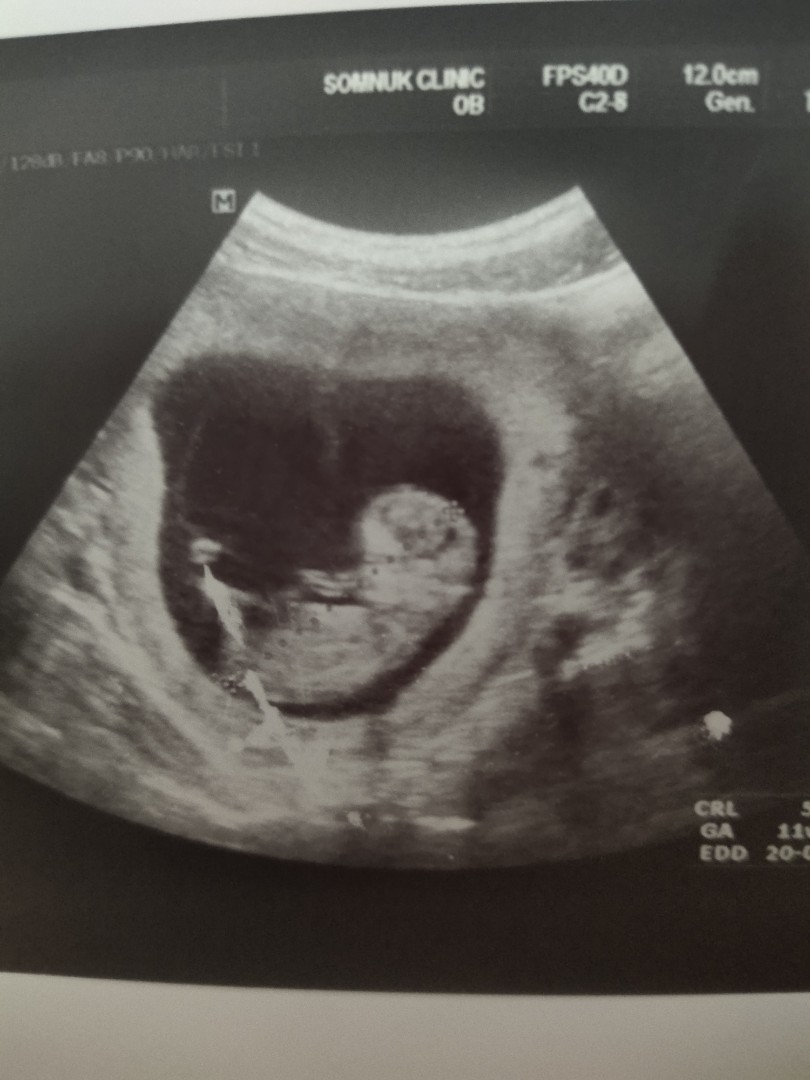

11 วีค